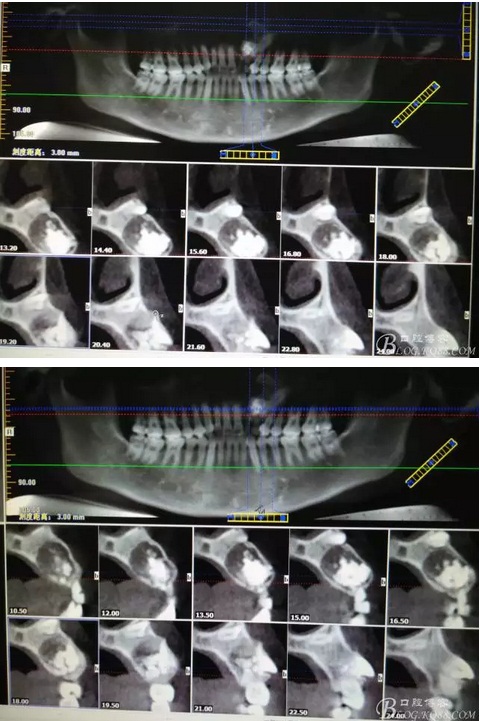

患者、女、曹xx、26歲,已婚。主訴:左側(cè)前牙區(qū)牙齦上有一疙瘩,要求治療。??茩z查:左側(cè)乳Ⅱ、Ⅲ滯留,頸部楔形缺損,探針不敏感。左側(cè)乳Ⅱ、Ⅲ唇側(cè)粘膜膨隆,表面結(jié)節(jié)狀,捫診質(zhì)地堅(jiān)硬,無波動(dòng)。CBCT檢查:左側(cè)乳Ⅱ、Ⅲ上方有一范圍約2.0x2.8cm的囊性改變,囊腔內(nèi)大量致密鈣化團(tuán)塊,密度高。22位于囊腔上方骨質(zhì)內(nèi),23移位至24上方區(qū)。診斷:1.牙瘤?2.牙瘤伴發(fā)囊腫?治療計(jì)劃:建議手術(shù)摘除?;颊咄馐中g(shù),并建議盡量保留左側(cè)乳Ⅱ、Ⅲ簽知情同意書。

圖1。術(shù)前的CBCT影像檢查:22位于鼻底下方,23位于24、25的根方。左側(cè)乳Ⅱ、Ⅲ根方顯示囊性改變,囊腔內(nèi)大量致密鈣化團(tuán)塊,密度高。